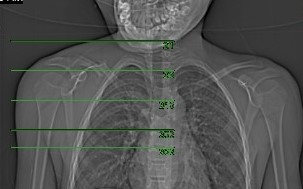

Topogram

• Position the patient in head first supine position.

• Align the patient’s shoulder in Mid-Sagittal plane of the table (if possible).

• Position the transverse laser light beam at the level of 1 inch above patient’s shoulder to start the shoulder topogram.

Topogram Parameters

• Topogram length: 256Ā cm

• Slice: 0.6 mm

• Scanning direction: Caudocranial

• Tube position: Top

• Stop the topogram scanning when the scanning reach / pass over the scapula angle.